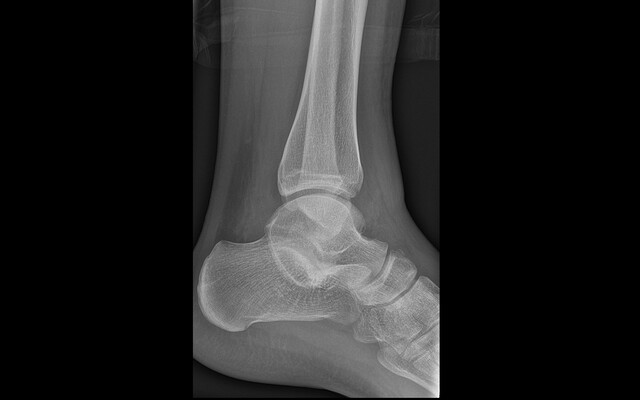

Dit artikel is alleen beschikbaar als PDF.Lees de PDF Artikelinformatie Online verschenen op 20 mei 1921 Citeer dit artikel als Ned Tijdschr Geneeskd. 1921;65:2301 Heb je nog vragen na het lezen van dit artikel? Check onze AI-tool en verbaas je over de antwoorden. ASK NTVG Ook interessant Nieuws Worst van ongewone samenstelling Vraag van de week Is dit een ongewone verzwikking van de enkel? Casuïstiek Een bloedzuiger als ongewone oorzaak van epistaxis Meer gerelateerd … Reacties Login om een reactie te plaatsen